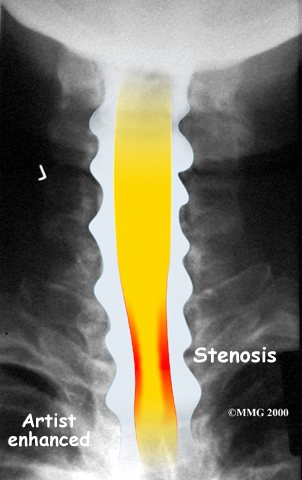

The spinal cord is a column of nerve tissue protected by a bony tube in the spinal column. Conditions that narrow the space in this tube put the spinal cord at risk of getting squeezed. This narrowing is called stenosis. When the narrowing occurs in the spinal column of the neck it is called cervical spinal stenosis, or cervical stenosis. Pressure against the spinal cord as a result of spinal stenosis causes injury to the spinal cord, which is termed myelopathy. Myelopathy is a condition that demands medical attention as it can cause serious problems including problems with the bowels and bladder, changes in the way you walk, and can affect your ability to use your fingers and hands.

The bony spinal canal normally has more than enough room for the spinal cord. Typically, the canal is just less than ¾ of an inch, or 17-18 millimeters around, which is less than the size of a small bottle cap. Spinal stenosis occurs when the canal narrows to around half an inch, or 13 millimeters or less. When the size drops even further, severe symptoms of myelopathy occur. The symptoms of myelopathy result from the actual pressure against the spinal cord itself as well as the reduced blood supply in the spinal cord as a result of the pressure.